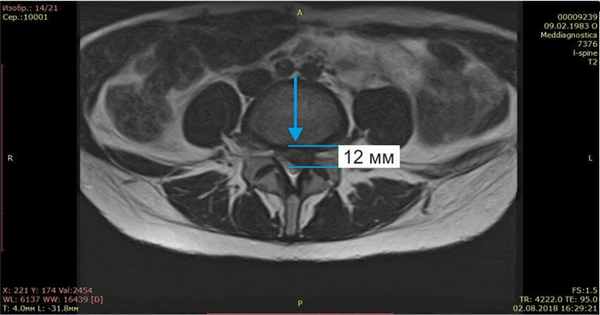

Осмотрели Ирину неврологически и ортопедически, исследовали позвоночник на МРТ и рентгене. Оказалось, что у нее очень большая левосторонняя грыжа размером 12 мм.

Контрольный МРТ, через 5 месяцев показал полное отсутствие грыжи диска (см. снимки Ирины ниже):

Обратите внимание на даты проведения МРТ в правом нижнем углу. МРТ исследования проведены на одном аппарате 1.5 теслы в клинике «Меддиагностика» в процессе лечения Ирины. МРТ позвоночника позволяет отследить динамику уменьшения грыжи диска.

Я сразу сделала МРТ, на котором обнаружилась межпозвоночная грыжа 12 мм, которая сдавливала седалищный нерв. Пропила таблетки противовоспалительные, витамины, но облегчения особого не было, боль в спине уменьшилась, но нога продолжала неметь.

После лечения назначили лечебную физкультуру для закрепления эффекта. В итоге моя грыжа с 12 мм уменьшилась до 2мм! Я очень рада, что попала в этот центр, где работают профессионалы своего дела, которые ставят людей на ноги и оказывают реальную помощь. Отдельно большое спасибо профессору Гонгальскому Владимиру Владимировичу. Это человек с большой буквы и профессионал своего дела. Рекомендую всем этот центр. Спасибо Вам большое, что Вы есть! С уважением, Ремига Ирина